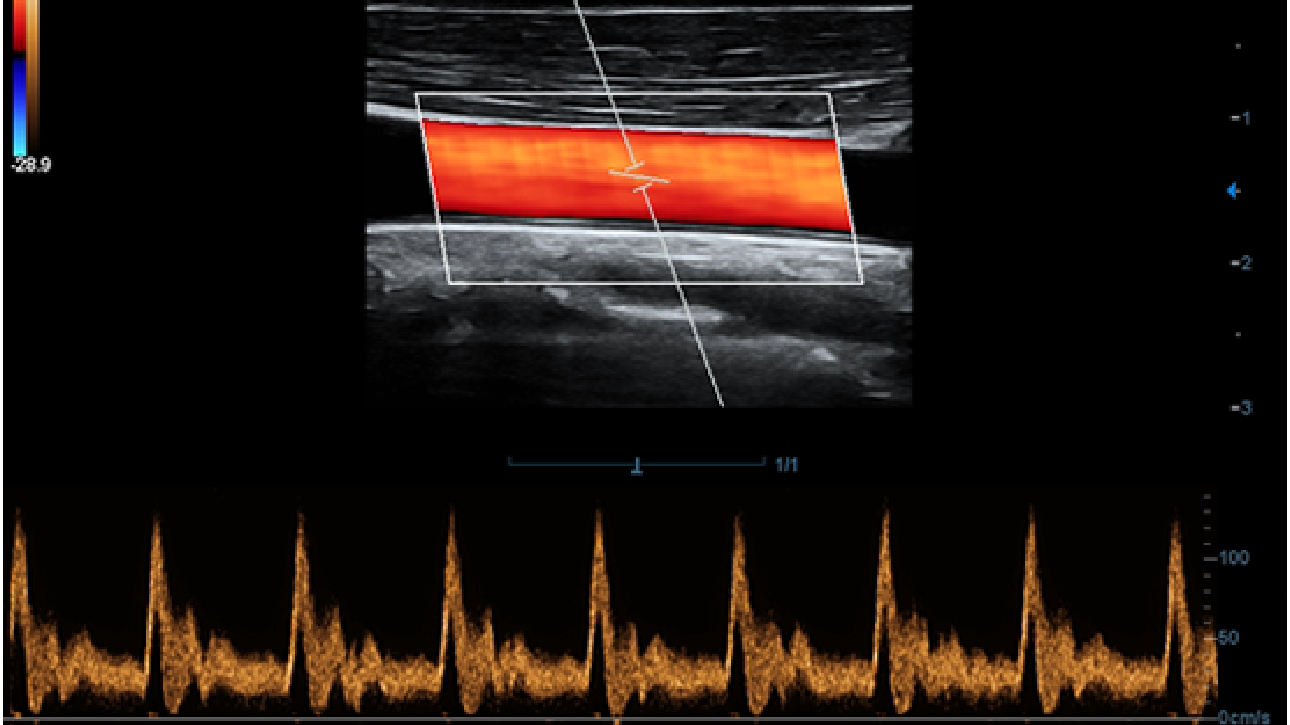

Klinische Bilder